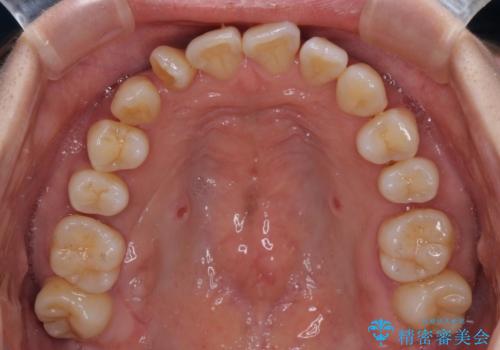

【モニター】上顎前突と奥歯の鋏状咬合 補助装置を用いたインビザライン矯正治療

- 前歯の歯列不正と奥歯の咬みにくさを気にして来院された患者様です。

インビザラインでの矯正治療を希望されていましたが、奥歯の咬み合わせがインビザライン単独では改善困難と判断されたので、補助装置を併用することとしました。

上顎最後臼歯は極端に外側を向いており、下顎骨に対して上顎骨が前方に位置していたため、補助装置により最後臼歯を一気に内側に引き込むとともに、上顎臼歯を後方移動させ、奥歯の咬み合わせが改善した後に、上下インビザラインにより歯列全体を整えていくこととしました。

奥歯の咬み合わせを事前に望ましい位置に改善したことで、インビザライン単独では改善が最も困難な状況を排除することができ、非常に理想的な仕上がりとなりました。